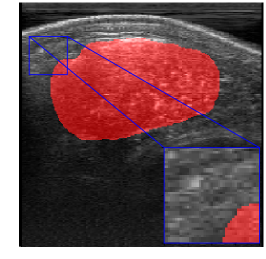

Rib Eye Area (REA). This image dataset consists of ultrasound images of the Longissimus dorsi muscle between the 11th and 13th ribs of cattle. The goal is to automatically calculate the rib eye area (REA), an important region for decision making during cattle breeding. The main challenge is the uncertainty in the REA annotation, since the image is noisy and even experts have difficulty in delimiting the borders of this region. Fig. 3 presents examples of images and the annotation made by a specialist. We can observe that some borders are absent and depend on the subjectivity and knowledge of the annotator. To evaluate the segmentation methods, 76 images with 309×213309213309\times 213 resolution were obtained and labeled by an expert. Due to the number of images, the division of the images in training and testing followed 5-fold cross-validation.

Refer to caption

Figure 3: Sample images from Rib Eye Area (REA) dataset.

REA dataset. This image dataset has high uncertainty during labeling due to noise from the ultrasound image. In some cases, the border of REA is not completely visible and must be estimated by the specialist. Therefore, the proposed approach becomes essential to obtain accurate segmentation at the edges. The segmentation examples in Fig. 6 show that the baseline was not able to define the REA correctly due to the uncertainty of the labeling. On the other hand, the proposed approach presents results close to the specialist in regions that the border needs to be estimated.